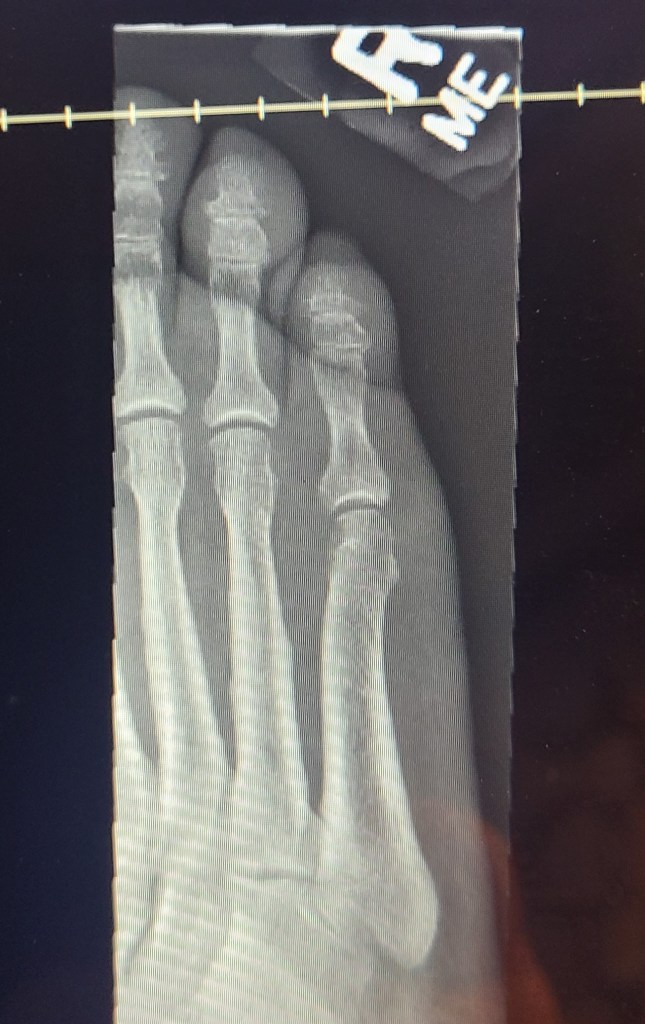

What else did I learn this week? Well, I learned that when you eat what some would consider too much organ meat you can get gout! We didn’t do a turkey for Thanksgiving, but I love giblet gravy and stuffing so I smoked turkey necks and heart/liver/gizzards in the week leading up to Thanksgiving. Thinking I was making good ‘lean’ choices, what I didn’t use for the gravy or stuffing I had for lunches throughout the week. In addition to those ‘good decisions’, I chose to have oyster shooters and a beautiful steamed clam dish last week. No dessert, no alcohol, just healthy eating. Friday I woke up and my toe was pretty sore, I didn’t remember banging it into anything and wondered if I got a bug bite of some sort overnight?? On Sunday night I felt like the Princess and the Pea (me being the Princess of course), the weight of the comforter on my toe kept my up half the night. By Monday, I couldn’t put on a shoe or a sock and with my upcoming surgery I thought I better go to the doctor and make sure I didn’t have some strange infection. After an xray to rule out I hadn’t somehow broken my toe, the blood work had the answer.